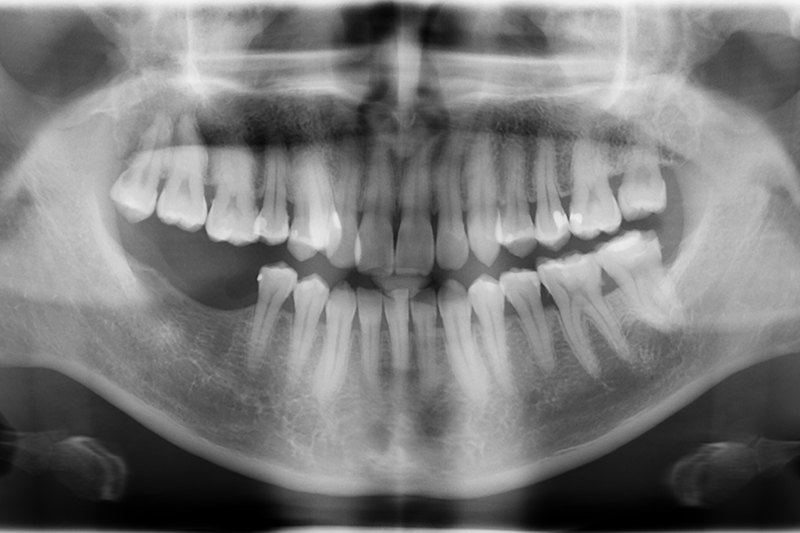

3D水雷射微創植牙 首頁 案例分享 植牙 3D水雷射微創植牙 治療前 治療後 聲明:本所療程皆由專業醫生評估後,依照個人口腔狀況進行治療。因每位患者個別狀況不同,術後狀況也不盡相同,需親來本所由醫生評估。